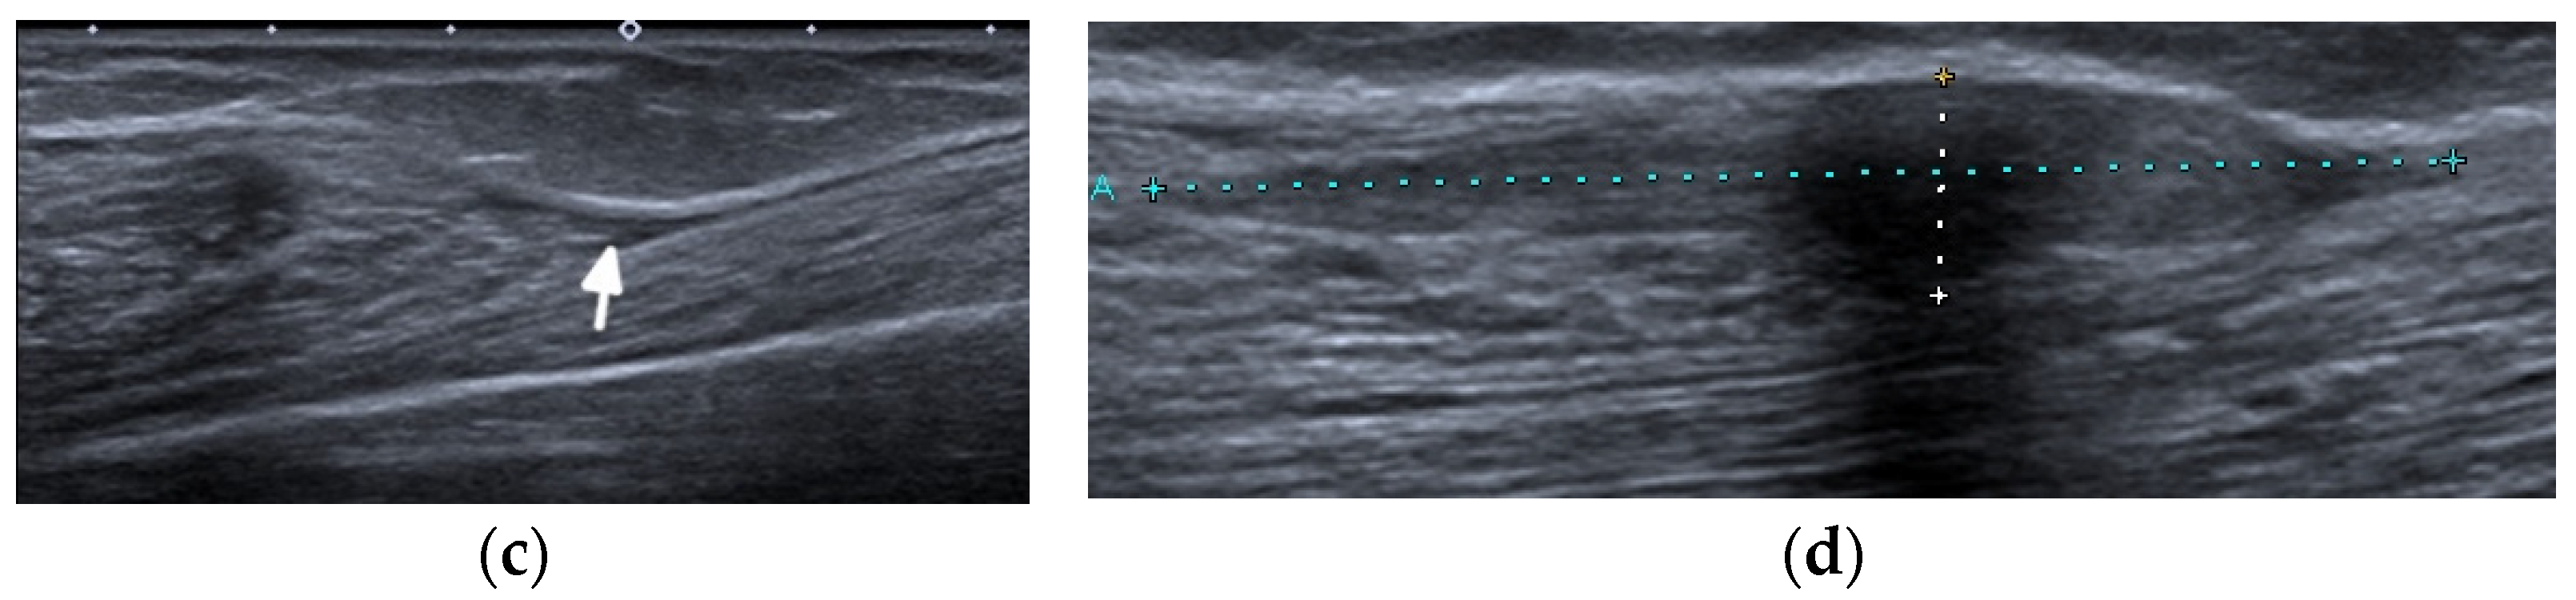

Figure 6.

A complete spontaneous tear of the right posterior tibialis tendon (PTT) 2 cm above the medial malleolus in a 46-year-old female with systemic lupus erythematosus. (a,b) short-axis gray-scale ultrasound (US) images of the medial aspect of the bilateral ankles show the normal echogenic fibrillar appearance of the healthy left PTT (a, arrow) compared to an enlarged, torn right hypoechoic PTT in the same region between calipers in (b). (c) Short-axis power Doppler US image of the affected right side shows hyperemia in the PTT tendon stump, with additional hyperemia in the tendon sheath consistent with tendinopathy and tenosynovitis. Two tiny red dots at the periphery of green Doppler box represent normal vessels.

Figure 7.

A complete tear of the proximal part of the bare tendon of the distal biceps brachii bilaterally in the same patient as in Figure 6. Short-axis (a,b) and long-axis (c,d) gray-scale ultrasound images of the bilateral elbow/distal arms show rupturing of the bilateral distal biceps tendons at the level of the myotendinous junction with hypoechoic proximal stums consistent with tendinopathy (arrows). In (c,d), note the retracted bilateral biceps muscles.